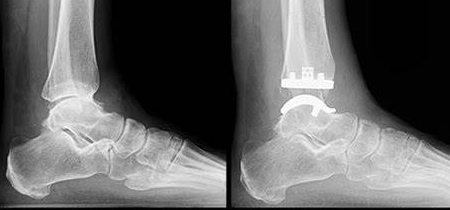

발목 치환술 (Total Ankle Arthroplasty)

적응증: 발목 전치환술은 일반적으로 말기 발목 관절염이나 심각한 발목 관절 기형이 있는 개인에게 권장됩니다.

절차: 이 수술에서는 손상된 발목 관절을 금속과 플라스틱 부품의 조합으로 교체하여 지지력과 향상된 이동성을 제공합니다.

혜택: 발목 교체는 통증을 완화하고 발목 움직임을 개선하며 환자의 걷기 능력과 충격이 적은 활동에 참여할 수 있는 능력을 향상시킬 수 있습니다.